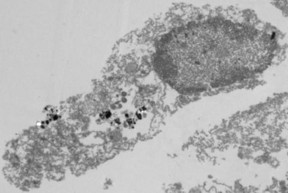

Disruption of the tumor cell due to treatment

with nanoparticles and visible light.

Disruption of the tumor cell due to treatment with nanoparticles and visible light.